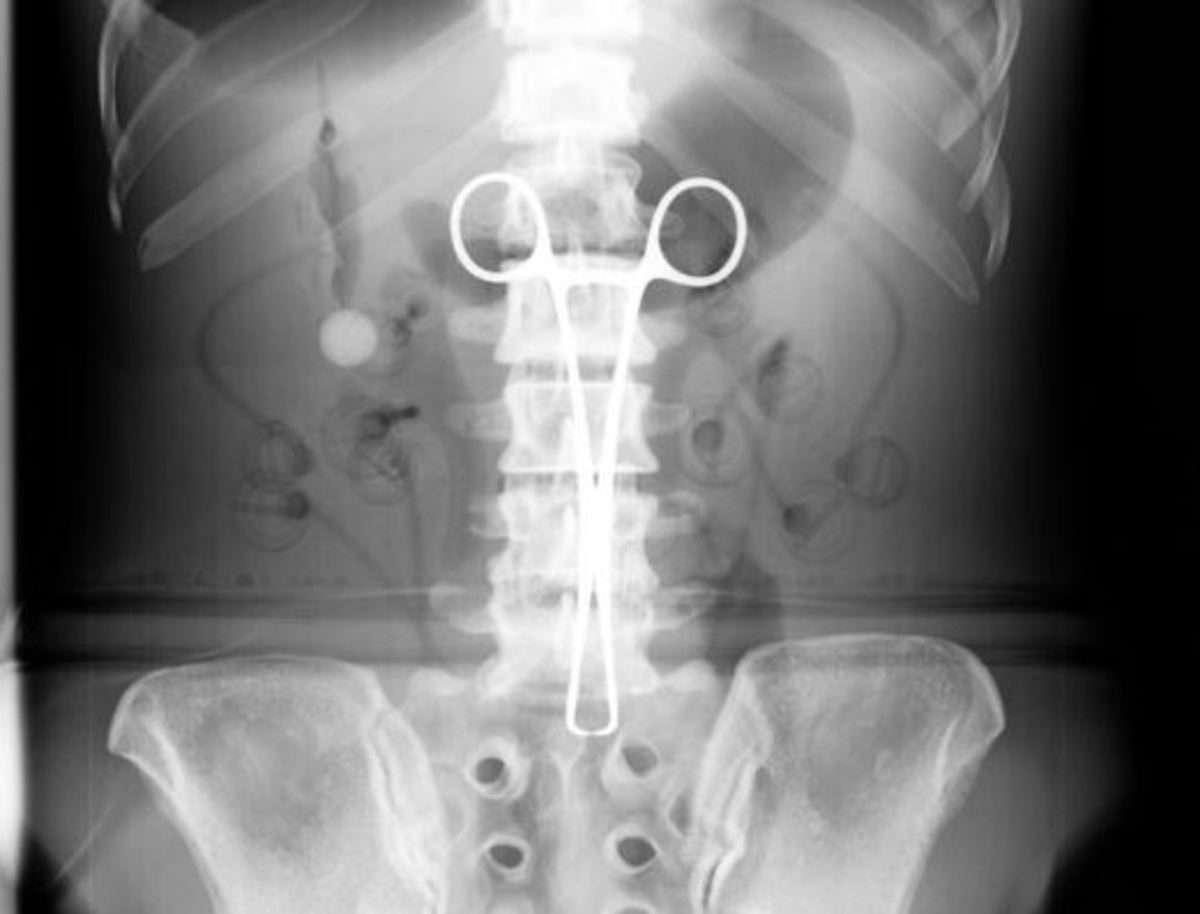

Γιατροί στο Βιετνάμ αφαίρεσαν μία χειρουργική λαβίδα από το σώμα ενός άνδρα όπου βρισκόταν χωρίς αυτός να το έχει αντιληφθεί επί 18 χρόνια, μετέδωσε η κρατική τηλεόραση VTV.

Ο 54χρονος Μα Βαν Νχατ δήλωσε ότι η λαβίδα είχε προφανώς ξεχαστεί μέσα στην κοιλιά του από το 1998 όταν είχε υποβληθεί σε επείγουσα χειρουργική επέμβαση έπειτα από τροχαίο ατύχημα.

Μία ακτινογραφία που έβγαλε τον περασμένο χρόνο έδειξε ότι για τον πόνο ευθυνόταν η λαβίδα.

Το εργαλείο μήκους 15 εκατοστών είχε σπάσει σε μικρά κομμάτια και είχε σφηνώσει στο στομάχι του Νχατ. Τα κομμάτια αφαιρέθηκαν με χειρουργική επέμβαση.